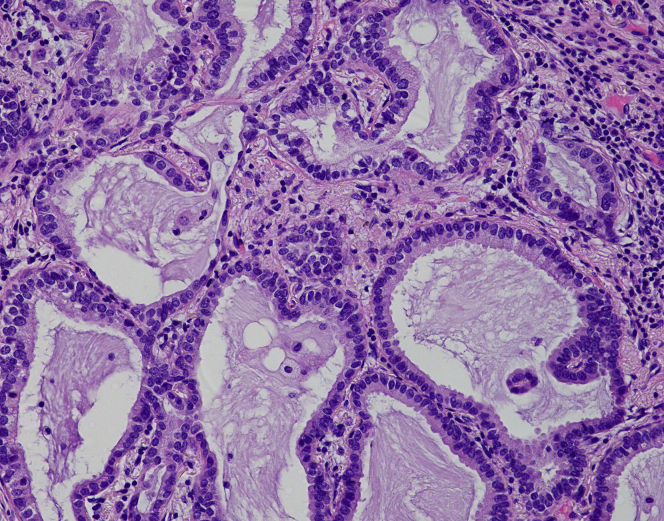

Pathologic staging was determined according to the eighth edition of the TNM classification of malignant tumors.18 All patients underwent pathologic examination using the WHO classification.19 The current pathologic grading was based on the predominant subtype, which are as follows: grade 1, lepidic predominant; grade 2, acinar or papillary predominant; and grade 3, solid or micropapillary predominant.5 The proposed pathologic grading was based on the following grading criteria, which was recently proposed by the IASLC: grade 1, lepidic predominant tumor, with less than 20A–E.% of high-grade patterns; grade 2, acinar or papillary predominant tumor, with less than 20% of high-grade patterns; and grade 3, any tumor with greater than or equal to 20% of high-grade patterns (solid, micropapillary, and/or complex gland).17 All patients were evaluated for lymphatic invasion (LY), vascular invasion (V), and pleural invasion (PL). The diagnosis of LY was based on the immunostaining results for D2-40 to validate the location of the lymphatic duct. To determine the degree of tumor invasion above the elastic layer of the vessels and the visceral pleura, the presence of PL and V is evaluated by means of elastic van Gieson staining. These pathologic diagnoses were made by experienced pathologists, which also included the authors (TK, KK, and YT). Representative images of each subtype are revealed in Supplementary Figure 1A–E.

Supplementary Figure 1A.

Supplementary Figure 1B.

Supplementary Figure 1C.

Supplementary Figure 1D.

Supplementary Figure 1E.